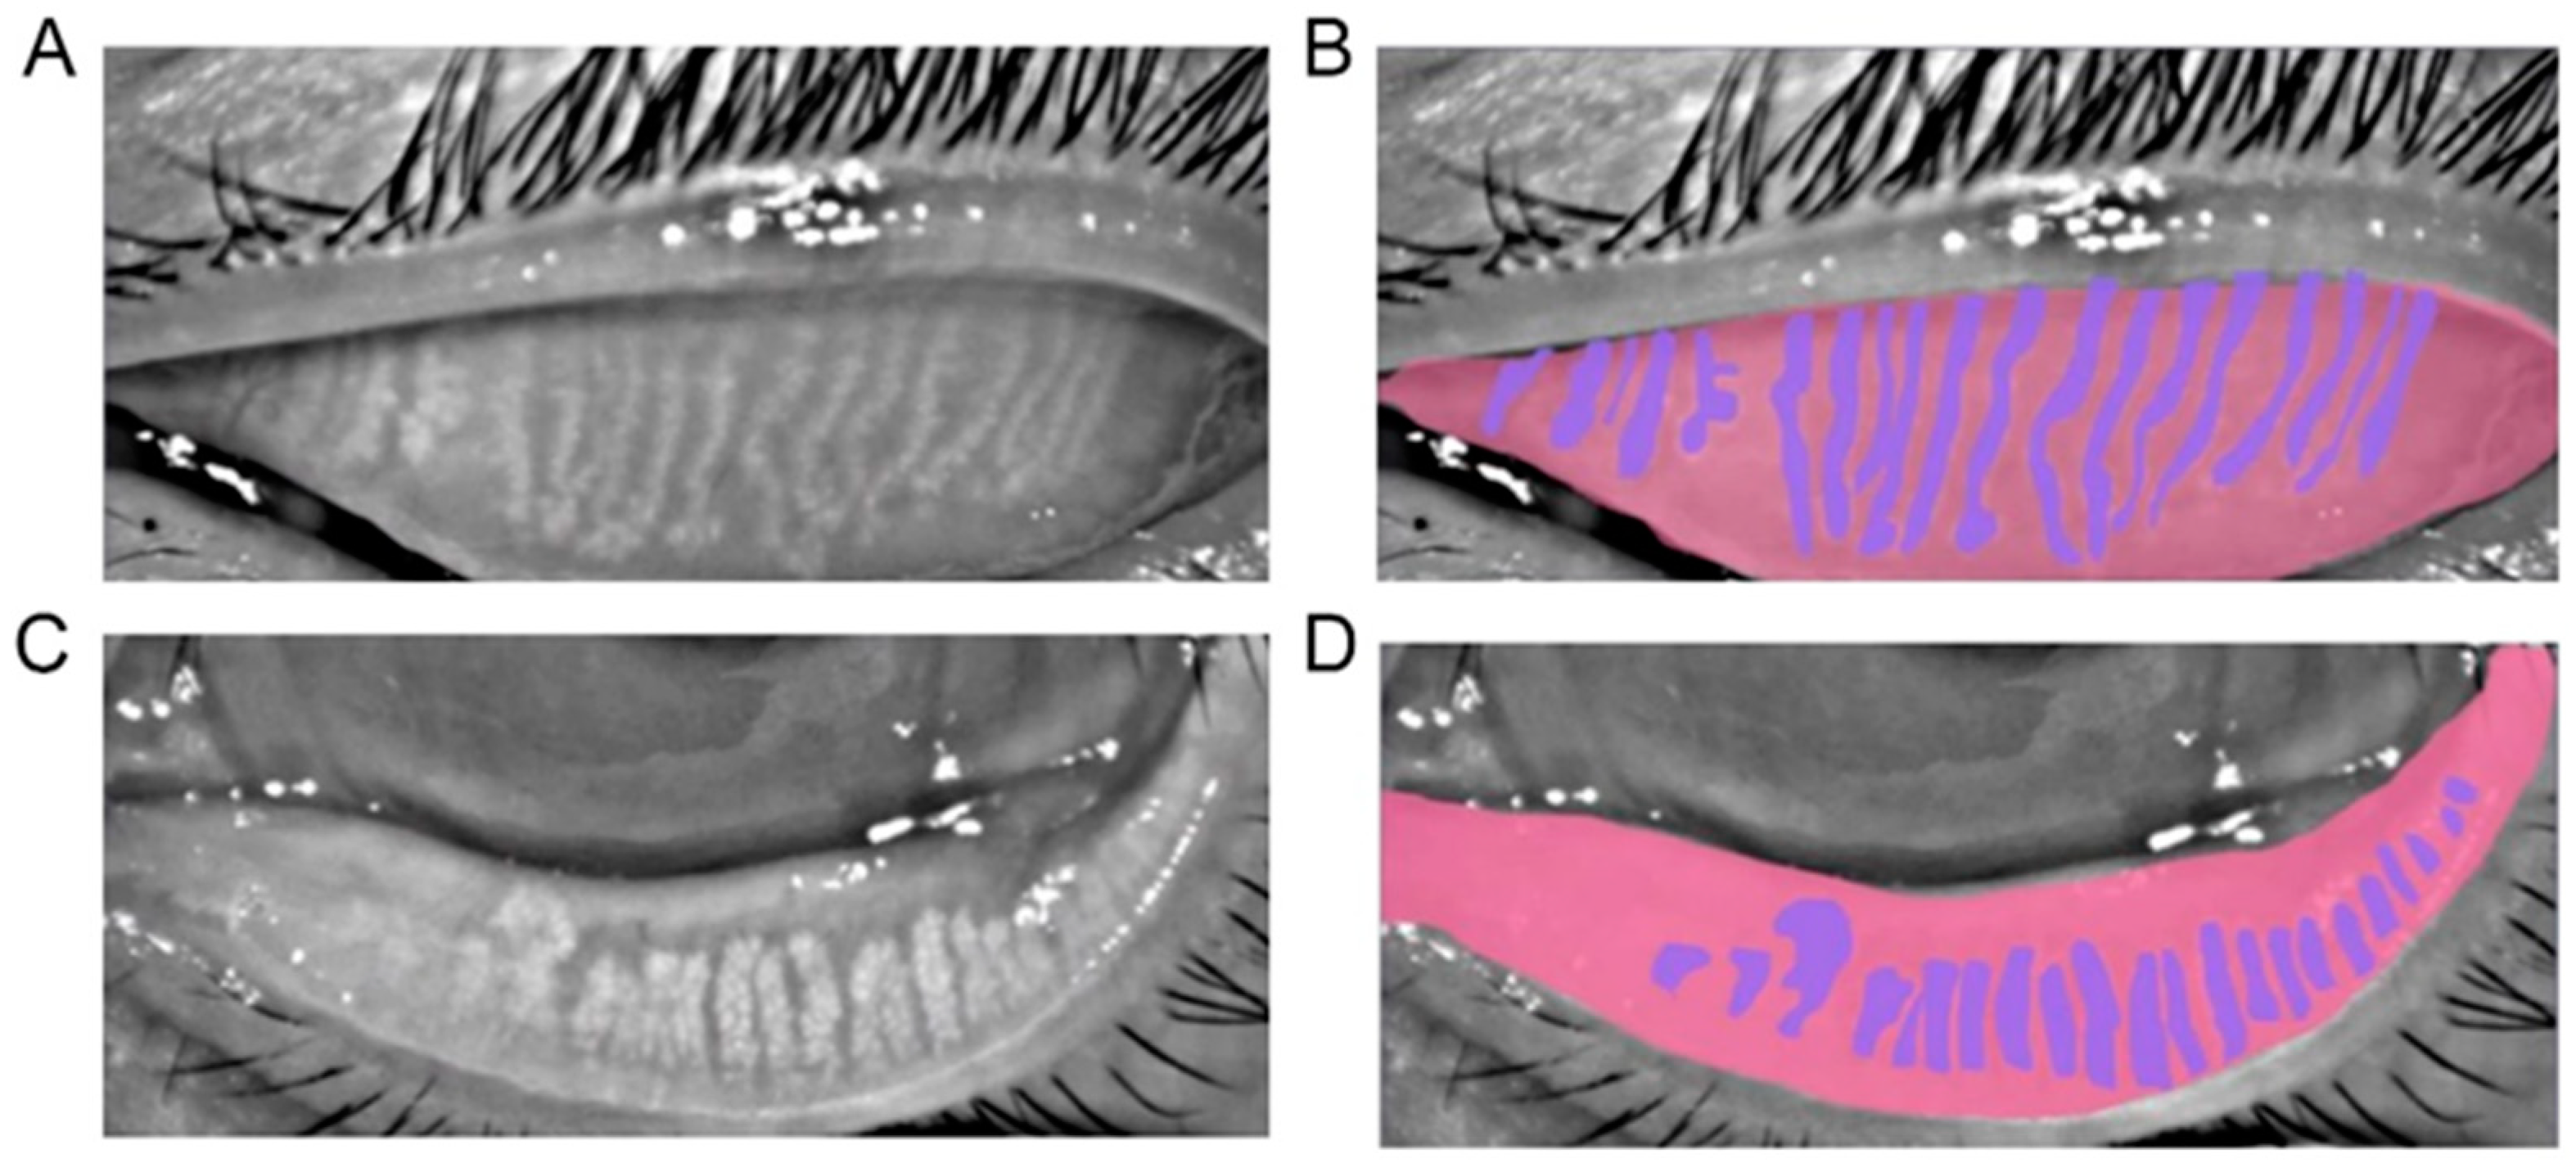

Figure 1 shows the representatives of a meibograph and its annotation.